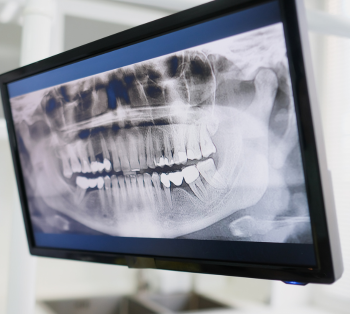

עקירת שן בינה היא פרוצדורה כירורגית שכיחה, המתבצעת כאשר שיני הבינה אינן בוקעות בצורה תקינה או כשהן גורמות לסיבוכים בריאותיים. שיני הבינה הן הטוחנות האחרונות שבוקעות לחלל הפה, לרוב בגילאים 16–23, ולרוב ישנן ארבע שיניים – שתיים בלסת העליונה ושתיים בלסת התחתונה.

כאשר שיני הבינה בוקעות בצורה מלאה ותקינה, הן עשויות להשתתף בתפקוד הלעיסה ואין הכרח לעקור אותן. עם זאת, במקרים לא מעטים שן הבינה אינה בוקעת כראוי, או ממוקמת בזווית שעלולה לפגוע בסביבה הדנטלית. במצבים אלו עשויה להינתן המלצה על עקירת שן בינה.